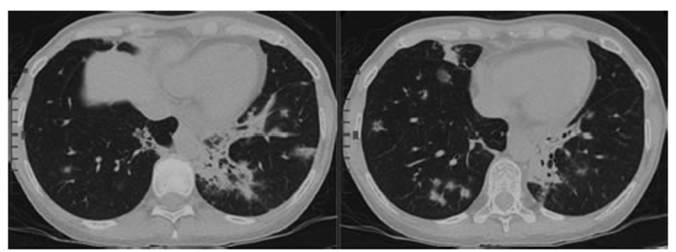

En TC, se observan múltiples infiltrados en

“vidrio esmerilado” peribroncovasculares de distribuÂción

central y periférica, con compromiso parcheado de ambos pulmones a

predominio bibasal y área consolidada con broncograma aéreo en segmento posterobasal

izquierdo.